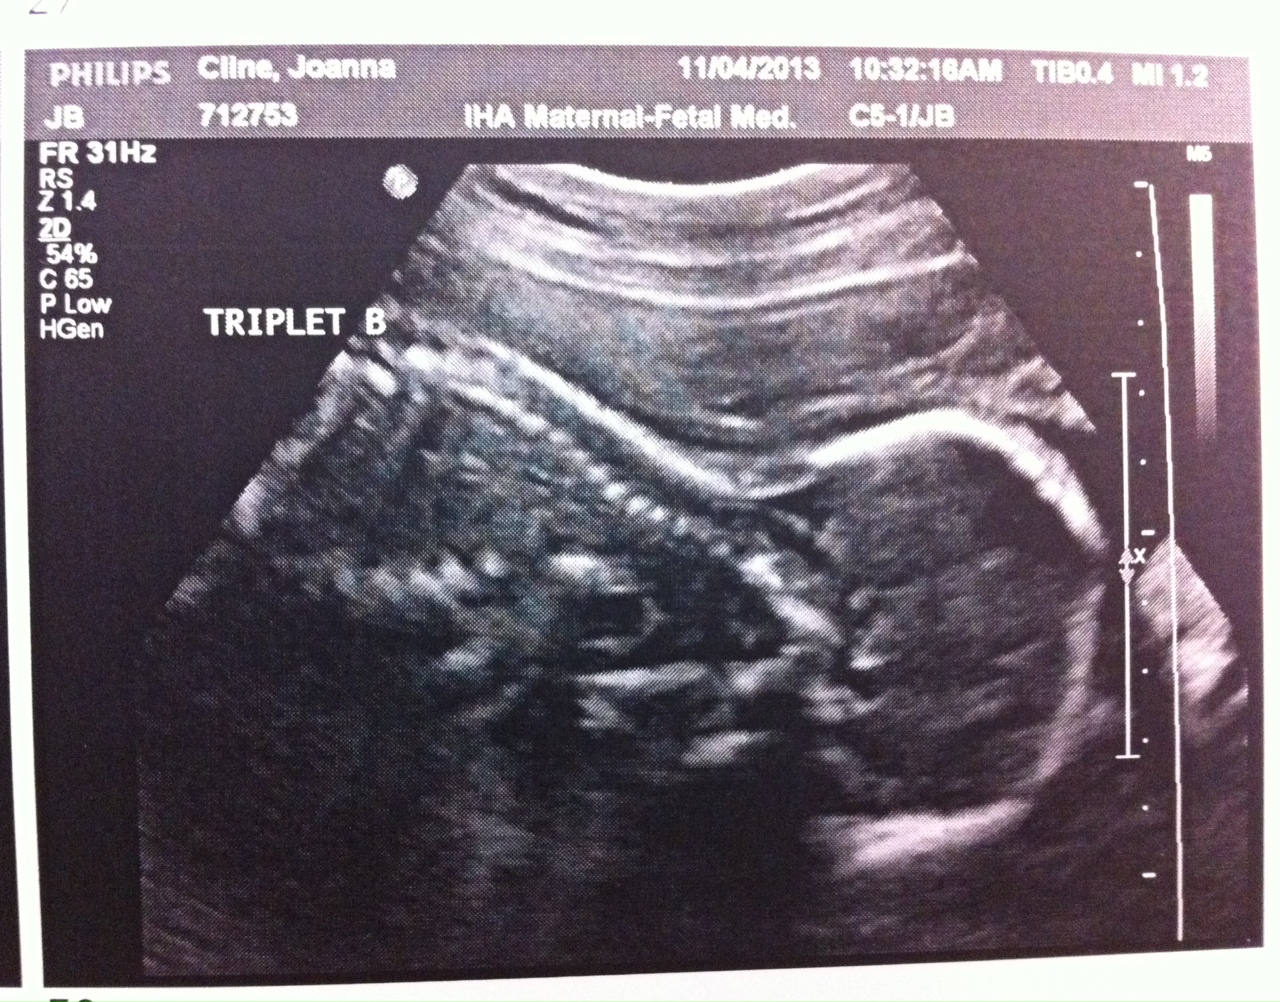

Obviously 24 weeks is still very early (and risky) and we don’t want these babies born yet but it’s still a great checkpoint in my pregnancy. Fortunately, everything looked fantastic at my appointment today. A, B and C looked great and my body is currently a fortress sealing them in where they belong.

Two photos are attached. This week, only A wanted to show his face. And I attached a V Day photo of me. I’m really not sure how my belly is going to get bigger but I’m told it will happen!